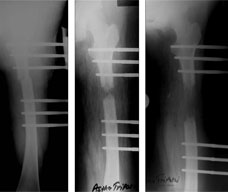

The x-ray picture on the left was taken after the surgery. It shows the osteotomy in the compressed state.

The x-ray picture in the middle was taken after distraction of around 14 days. The gap created at the osteotomy site gradually fills up with new bone called regenerate.

The x-ray picture on the right was done after completion of distraction of 6cms, which took a little more than 60 days. The distraction gap is showing some fluffy kind of shadow, this is the regenerate which has not mineralized completely yet and hence doesn't show up well on the x-ray. |